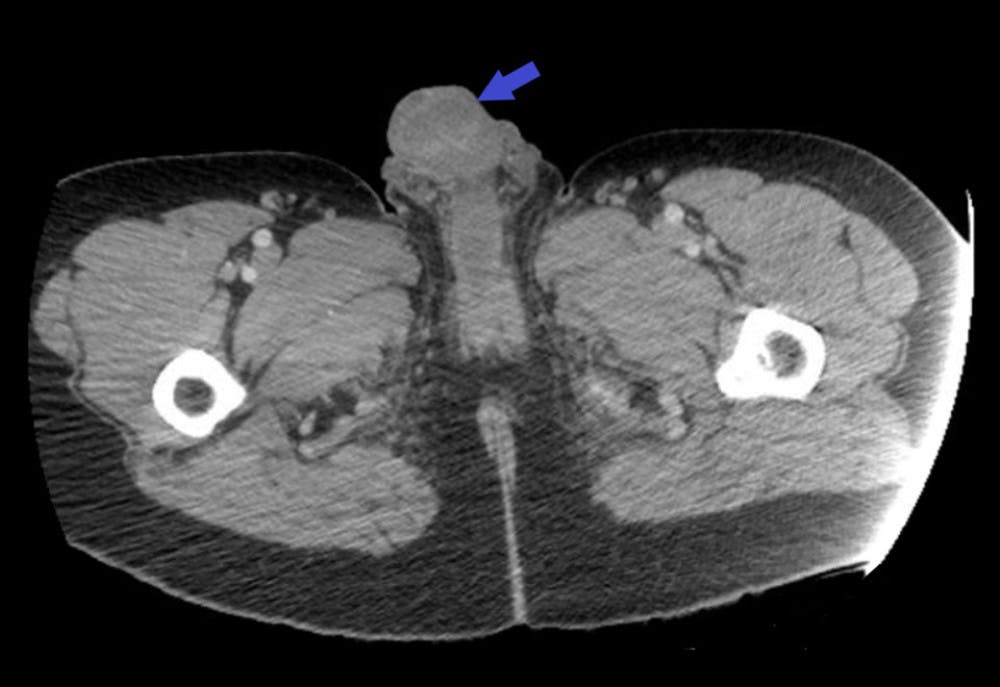

I journalen er der også tilføjet billeder, som viser, hvordan mandens penis reagerede efter indsprøjtningen.

De billeder har vi dog valgt at skåne jer for. Men de kan findes i journalen.